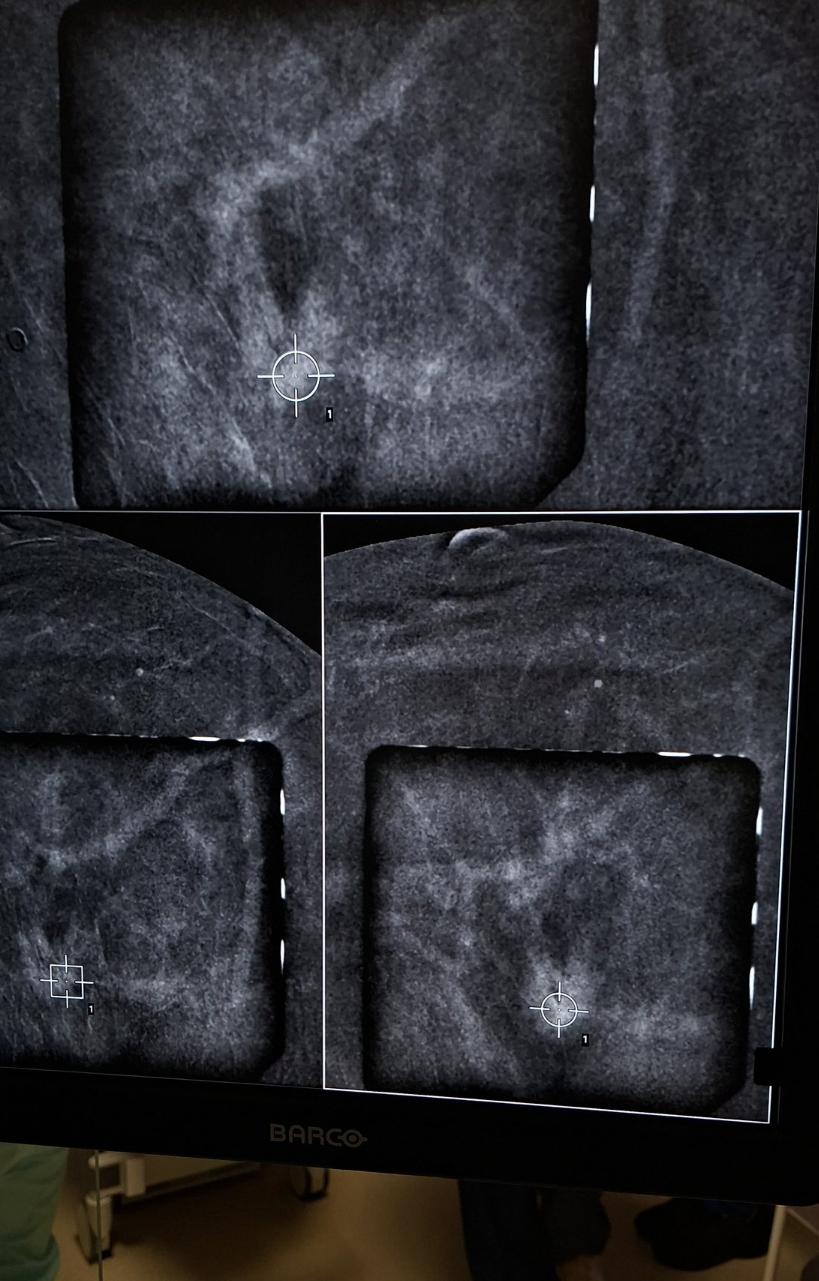

Medicul Carmen Lisencu a efectuat prima biopsie ghidată prin CEM (mamografie cu substanță de contrast), utilizând echipamentele moderne disponibile în cadrul institutului. Procedura reprezintă o alternativă mai accesibilă la biopsia ghidată prin RM (rezonanță magnetică), o metodă adesea mai costisitoare și mai greu de disponibil.

Biopsia ghidată prin CEM (Contrast-Enhanced Mammography) este o tehnică modernă de investigare care combină mamografia clasică cu administrarea unei substanțe de contrast pentru a evidenția zonele suspecte din sân. Aceasta este folosită în special atunci când leziunile nu sunt vizibile clar prin metode obișnuite, dar apar pe imaginile mamografice cu contrast.

Procedura este considerată o variantă adaptată a biopsiei stereotactice, fiind utilizată pentru a preleva probe din leziuni care pot fi observate doar pe imaginile CEM. În practică, metoda oferă o alternativă eficientă la biopsia ghidată prin RMN, fiind mai accesibilă și mai rapidă.